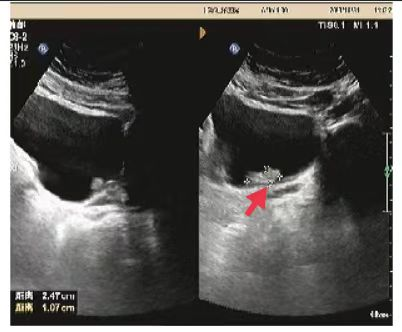

02、**男士,78岁

于2023年11月1日在邯郸仁泰西区体检,膀胱彩超检查提示:膀胱内见大小约2.5*1.1cm低回声,可见血流信号。首次回访2023年11月1日,通知客户到三甲医院进一步检查。2023年11月6日跟踪回访,客户家属告知,就诊市第一医院,诊断膀胱癌早期,实施微创手术切除,后期继续化疗。